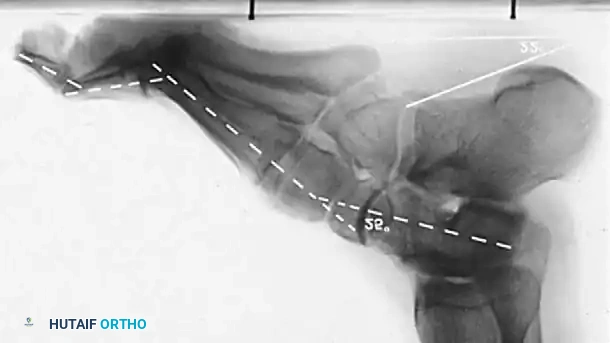

* Meary’s Angle (Talus-First Metatarsal Angle): Normally 0 degrees. In a cavus foot, the angle is convex upward (apex dorsal), indicating midfoot/forefoot equinus.

* Calcaneal Pitch: Normally 15 to 20 degrees. In a cavus foot, it is significantly increased (>30 degrees).

* Hibbs Angle: The angle between the longitudinal axis of the calcaneus and the first metatarsal. It approaches 90 degrees in severe cavus (normal is ~140 degrees).

Fig. 7: Standing lateral radiograph demonstrating an increased calcaneal pitch and a severe apex-dorsal Meary's angle.